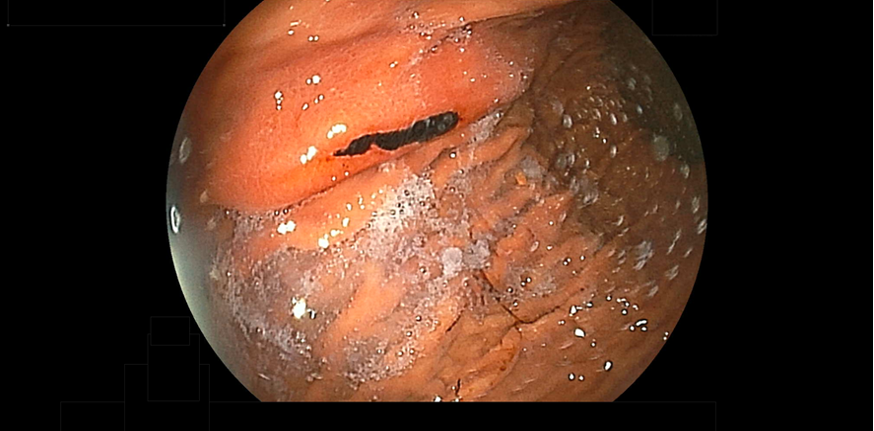

急性胃炎とは、様々な原因で胃の粘膜が急激に炎症を起こす病気です。突発する上腹部痛、吐き気、嘔吐、時に吐血・下血の症状を伴って発症します。内視鏡検査で、胃粘膜に急性の炎症性変化、出血、潰瘍性変化が観察されるものを、急性胃粘膜病変と呼び、過度の飲酒や刺激の強い食べ物の摂取、ストレス、ヘリコバクター・ピロリの感染、アレルギー、鎮痛薬・ステロイド・抗菌薬などの薬剤が原因と考えられています。内視鏡検査が普及しており、粘膜の炎症状態を詳しく観察できます。